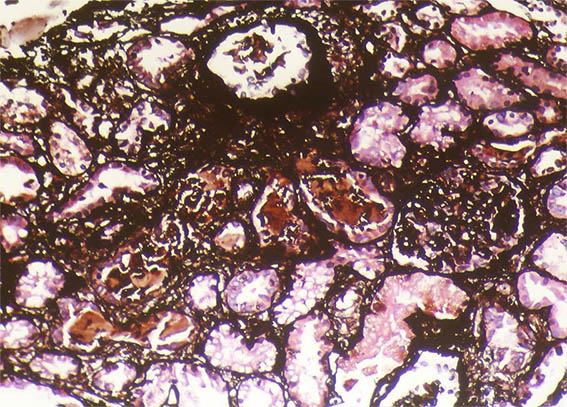

Un hombre de 40 años presentó falla hepática aguda severa secundaria a infección por virus de la hepatitis A, y lesión renal aguda.

Pruebas de laboratorio más relevantes: trombocitopenia (76.000), hiperbilirrubinemia (7,1 mg/dL), transaminitis (1.830 U/L and 2.320 U/L) y elevación del INR. Creatinina sérica: 5,2 mg/dL, BUN: 78 mg/dL, proteinuria: 100 mg/dL, sin microhematuria.

Se hace biopsia renal. Observe las imágenes.

Figura 1. H&E, X100.